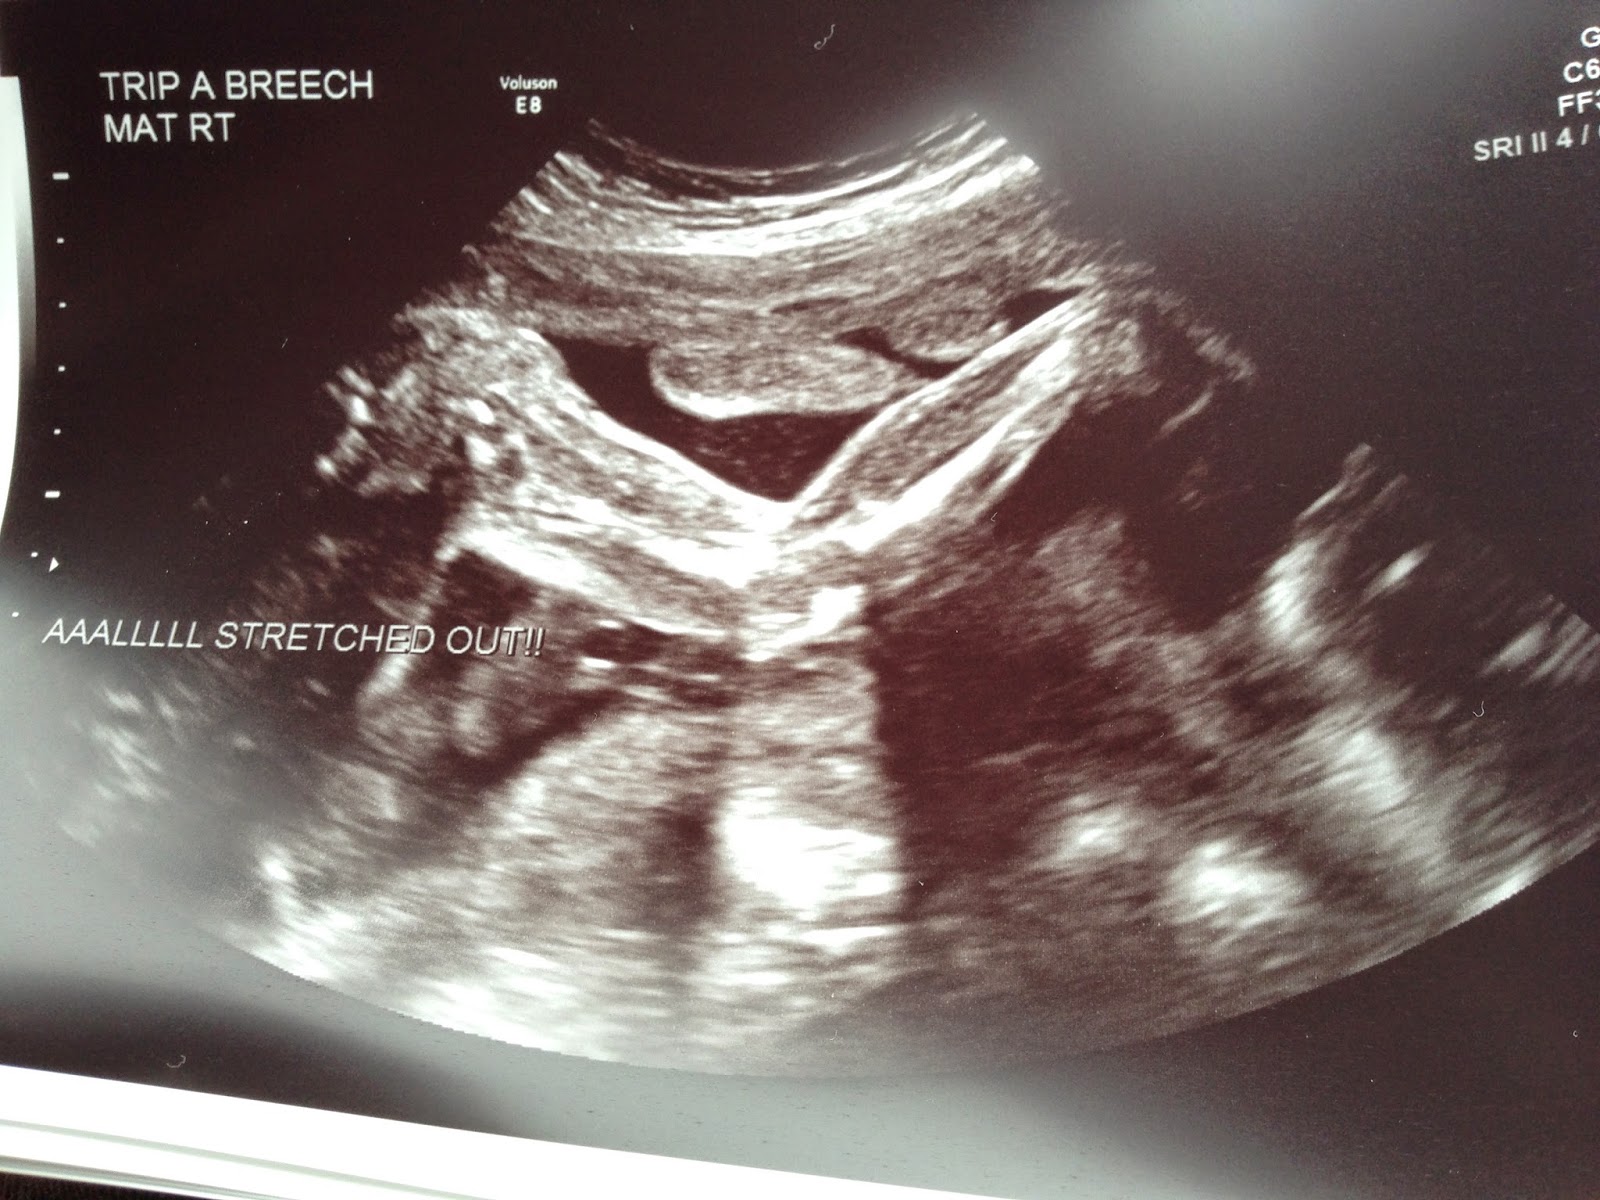

Check out her long, stretched-out leg!

Every 3 weeks we have lengthy appointments for growth scans where they measure every major body part on each baby. Today that took about an hour and forty-five minutes. For me it's not easy lying on a little table that long, but I powered through!

This little girl could not sit still today. You would think it would be difficult for the sonographer to get her measurements, but she said with all babies she probably had the best anatomy scan ever.